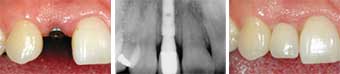

Tek diş implant uygulaması

Cenap Adaş İmplantlar